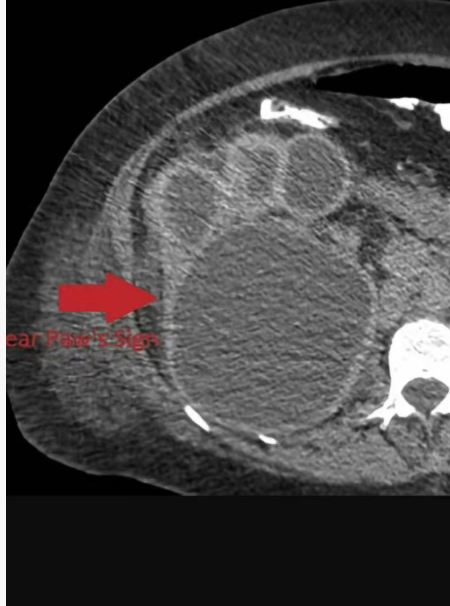

"熊掌征"(bear paw sign)是指在断面影像上肾盂粘连收缩,而肾盏扩张,肾皮质变薄,扩张的肾盏形似熊脚掌的征象,它是黄色肉芽肿性肾盂肾炎的一个重要特征性征象。

"熊掌征"表现为以肾盂肾盏为中心肾实质内多发囊性占位,其中部分囊为结石梗阻所致的肾积水,部分为黄色肉芽肿的脓腔;通常肾盏扩张为主,肾盂扩张常常不显,增强后,病变实性部分均匀强化,坏死区无强化,低密度区边缘环形强化。患肾体积增大或局限性隆起。常常伴有集合系统结石;肾皮质变薄;肾窦脂肪组织减少,多为慢性炎性反应性纤维组织增生所替代;肾周筋膜增厚、肾周间隙渗出积液,严重时可形成脓肿累及腰大肌。腹部X线平片典型的表现是受累的肾脏增大并有鹿角状结石,同侧腰大肌边缘模糊。超声显示肾脏轮廓变形,正常结构消失,中央可探及结石声影。